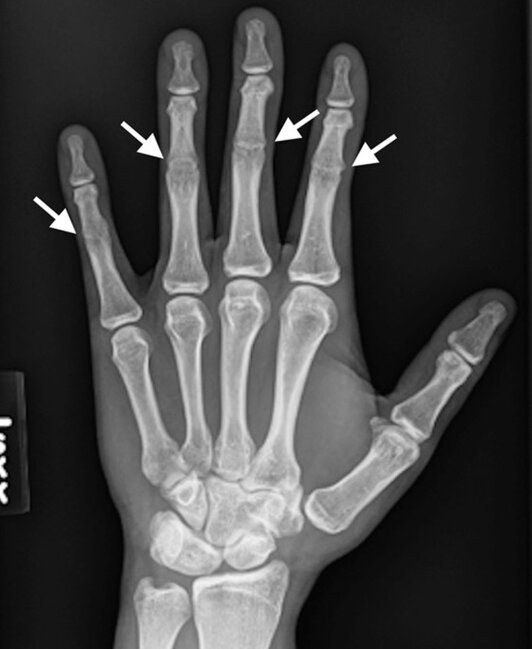

Bu adamın əlində orta oynaqlar YOXDUR - FOTO

Bu adamın əlində orta oynaqlar YOXDUR - FOTOBarmaqlarınızda orta oynaqlar olmadan özünüzü təsəvvür edə bilərsiniz? Həyatınızın nə dərəcədə çətinləşəcəyini anlatmağa ehtiyac yoxdur. Barmaqlar bükülmədən heç yazı yazmaq belə, mümkün deyil.

Bu adamın əlində orta oynaqlar YOXDUR - FOTOQeyd edək ki, sümük inkişafına təsir edən bu nadir irsi xəstəlik simfalangizm adlanır.